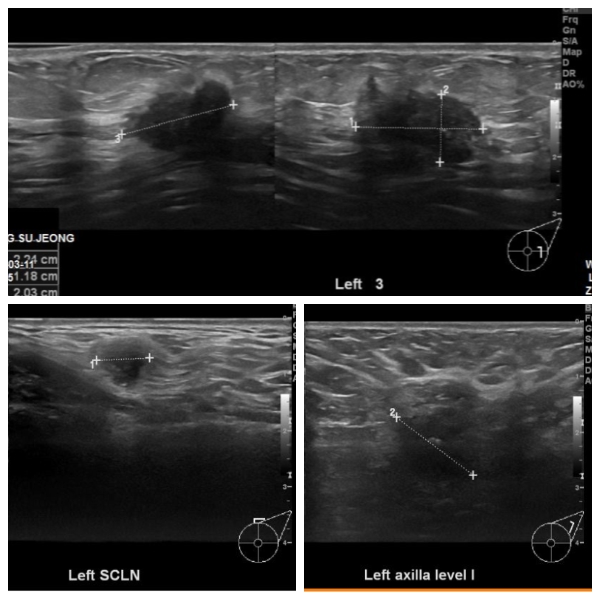

본원에 내원하신 40대 환자분이십니다.

좌측유방에 혹 조직검사와

좌측쇄골아래와 겨드랑이에 림피절비대소견보여

세침검사 시행하였고

결과상 침윤성유관암진단되었고 림프절까지 전이되어있었습니다.